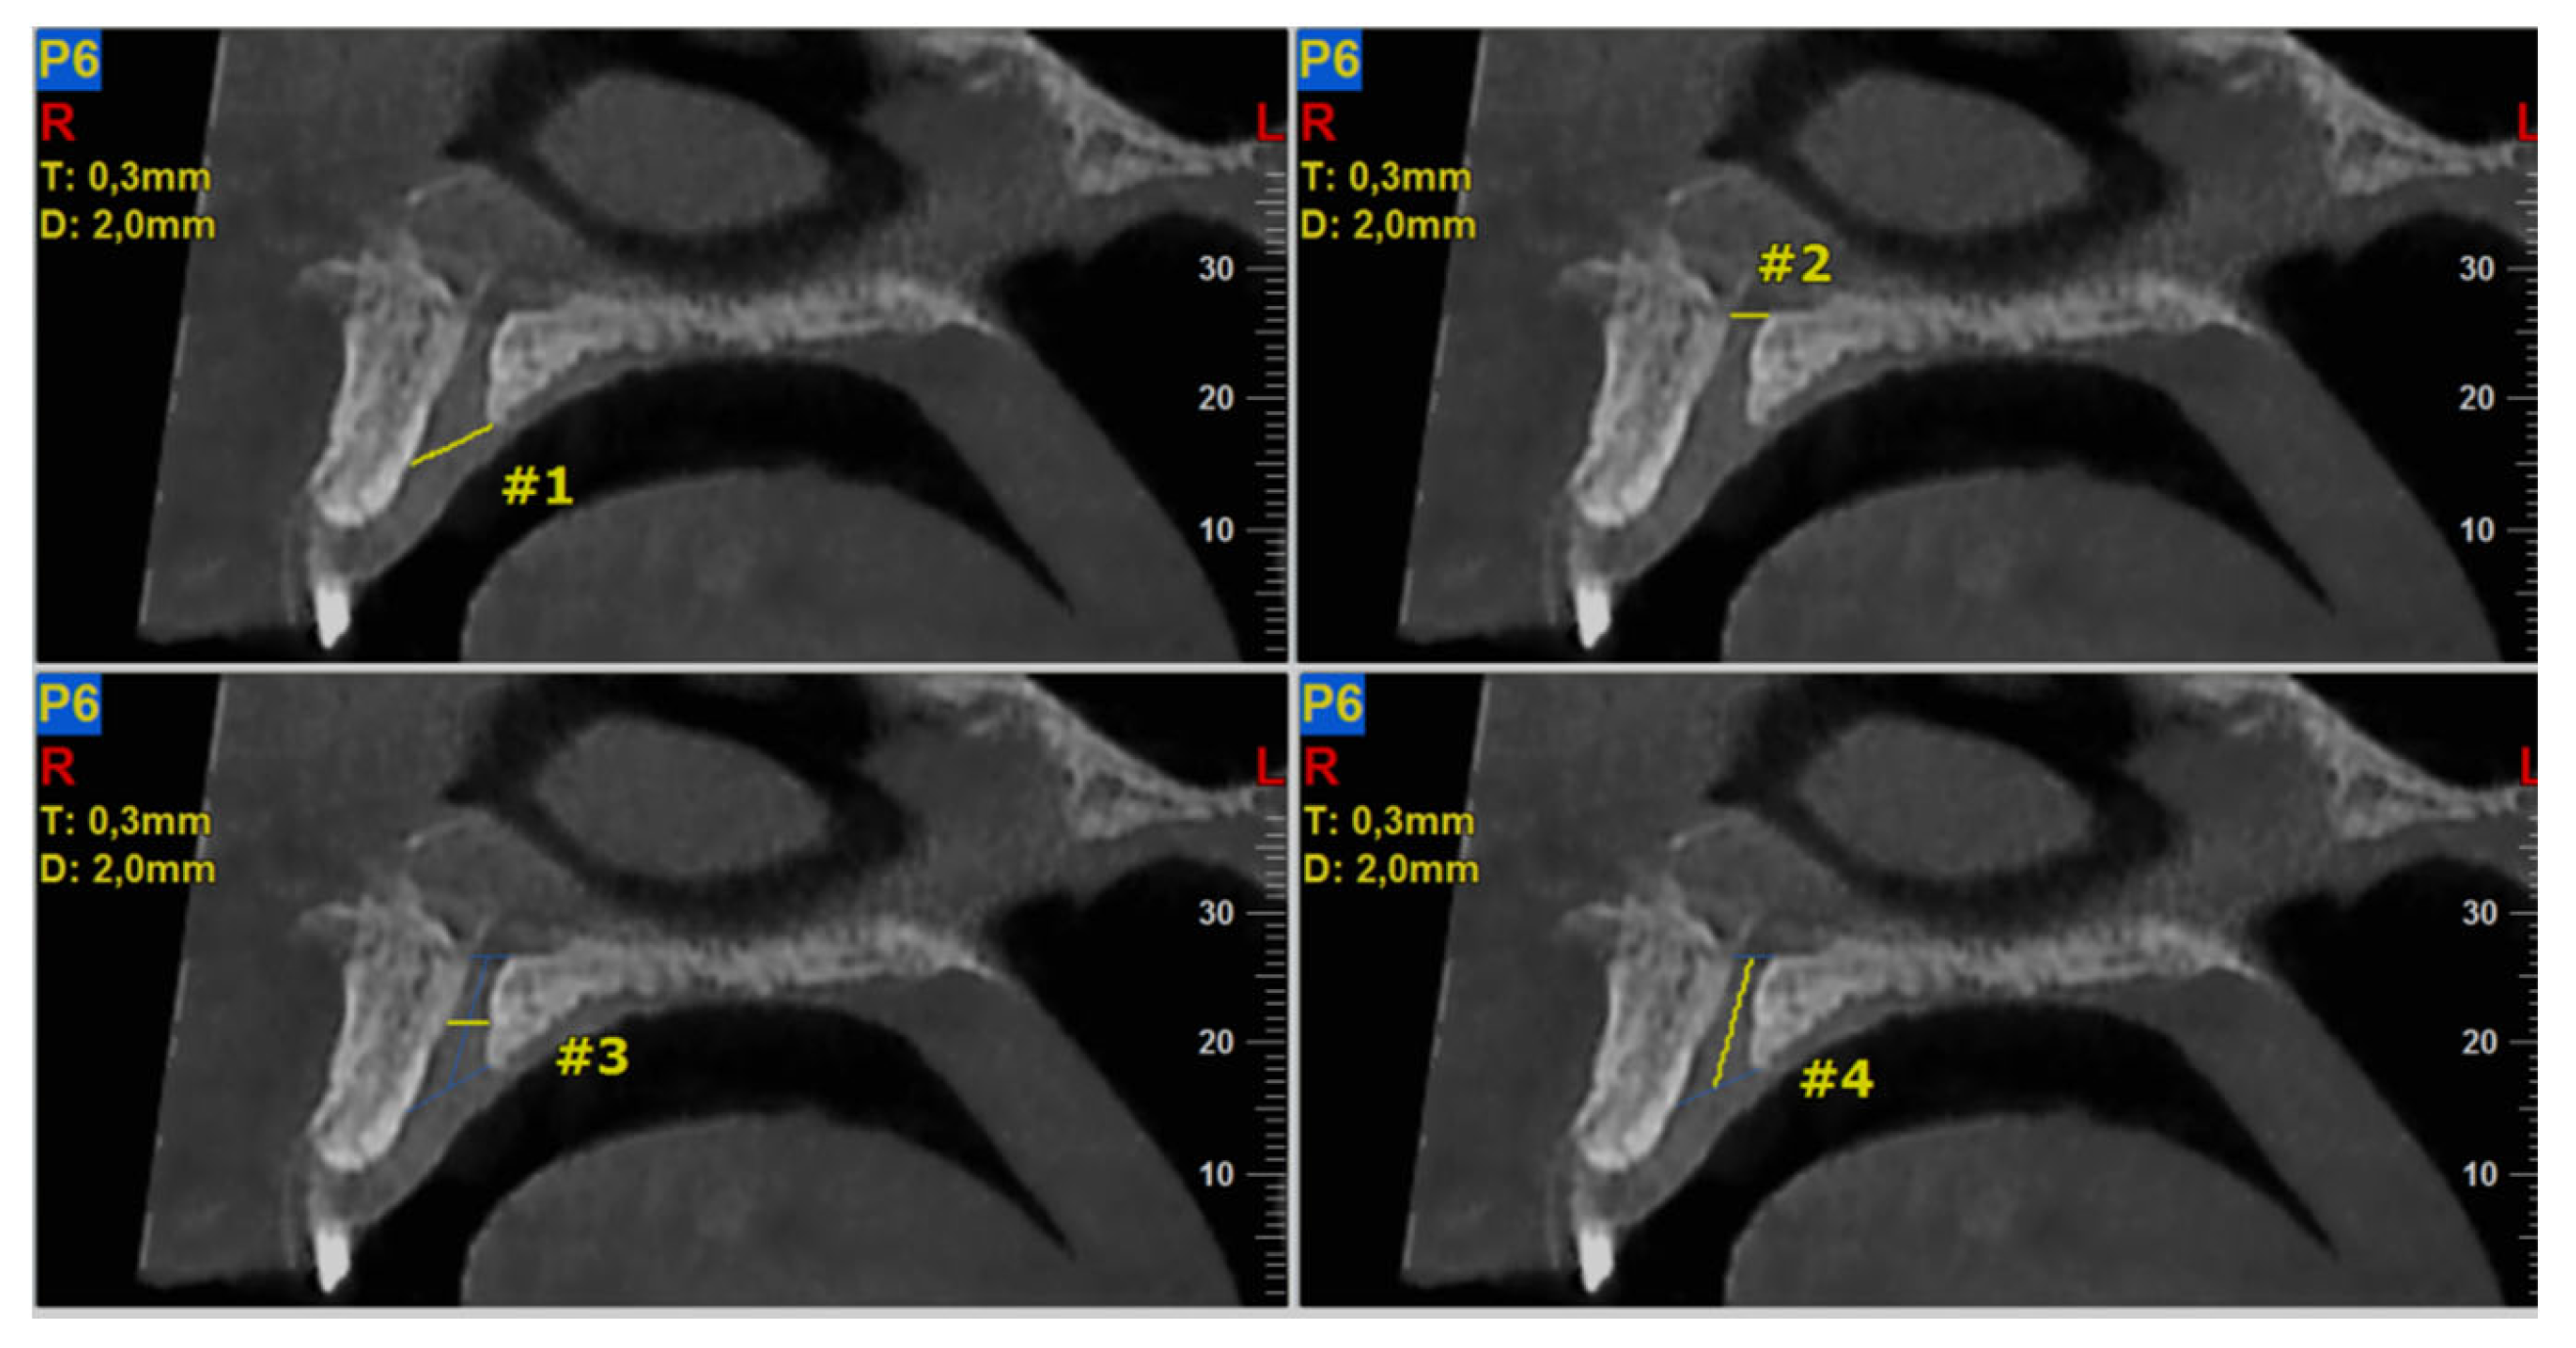

The required measurements (in mm) were: (#1) the diameter of IF, (#2) the diameter of SF, (#3) the diameter in the middle of the NPC, (#4) the total length of the NPC, (#5) the crestal distance from the buccal border of the IF to the facial aspect of the BOP, (#6) the distance midway from the buccal bone wall of the NPC to the facial aspect of the bone wall, using a horizontal line from the palatal border of the IF, and (#7) the most cranial distance from the buccal border in the middle of the NPC to the facial aspect of the buccal bone wall. These were measured on the reconstructed sagittal CBCT images (Figure 1 and Figure 2). All measurements were performed using the manufacturer’s specialized computer software (NNT v.6.2, Verona, Italy) [6,27,28]. Anatomical types of NPC were also recorded and classified as: a single canal (A), two parallel canals (B), variations of the Y-type of canal with one IF and two or more SF (C). This was performed on the reconstructed coronal CBCT images (Figure 3) [6,27,28].

Figure 1.

The following landmarks were selected for nasopalatine canal (NPC) analysis of the sagittal cone beam computed tomography (CBCT) images (all measurements in mm): #1—the diameter of IF, #2—the diameter of SF, #3—the diameter in the middle of the NPC, #4—the total length of the NPC.